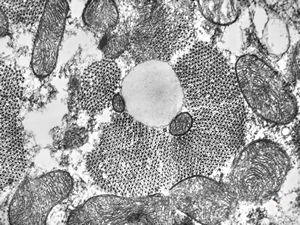

M,12y. | multiple mitochondria in oncocyte - Ewing sarcoma